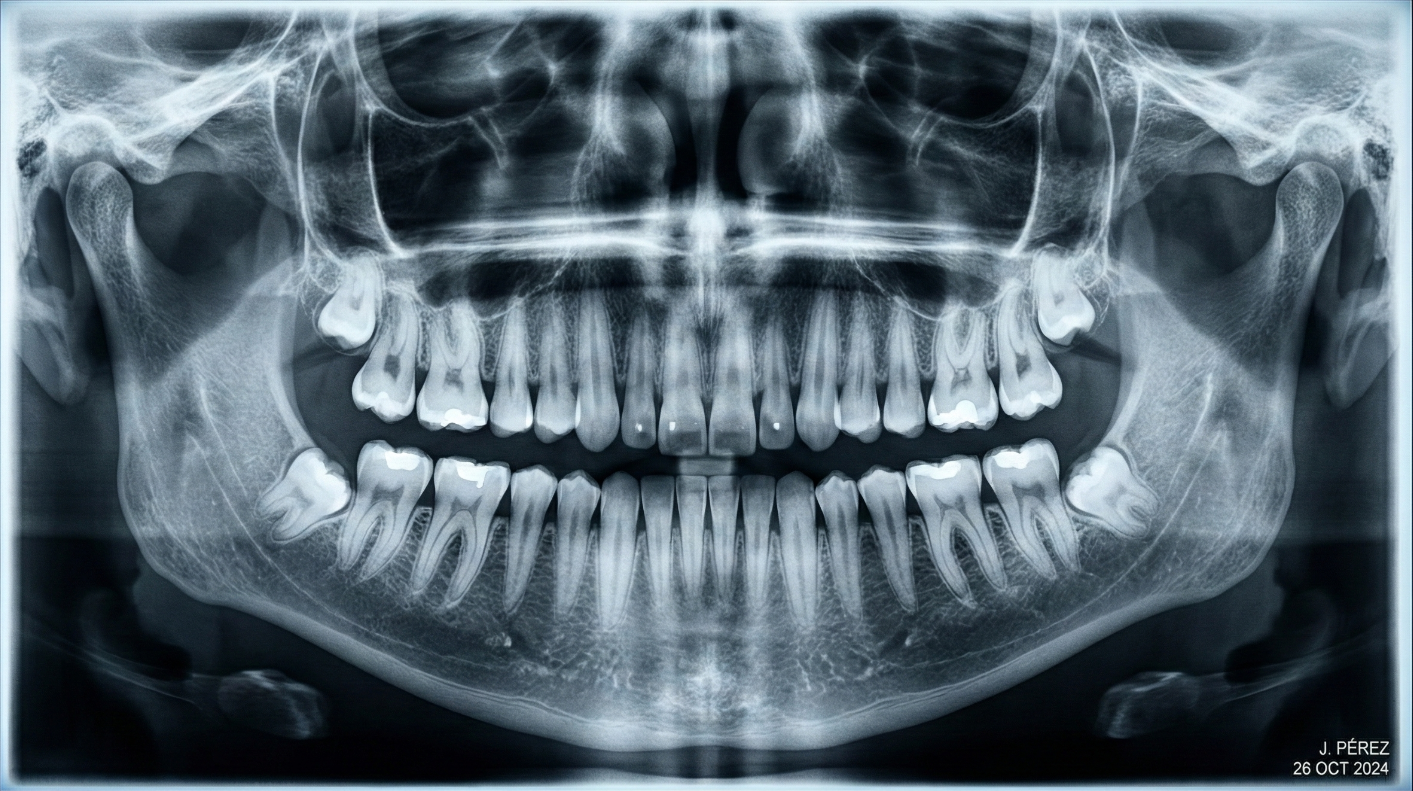

Radiografías Panorámicas

Capturan una imagen completa de la boca, incluidos dientes, mandíbulas y senos maxilares. Entrega un contexto general de la boca del paciente.